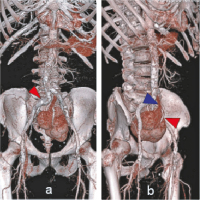

Abbildung 4a-b: CT-Angiographie (VRT). (a): Ansicht von ventral. Große, plumpe Niere mit lobulierter Oberfläche und Lage in Projektion auf die Mittellinie, der rote Pfeil markiert den proximalen Stent; (b): Ansicht von rechts lateral. Ventral gelegener Hilus mit V. renalis (blauer Pfeil) und A. renalis (roter Pfeil).